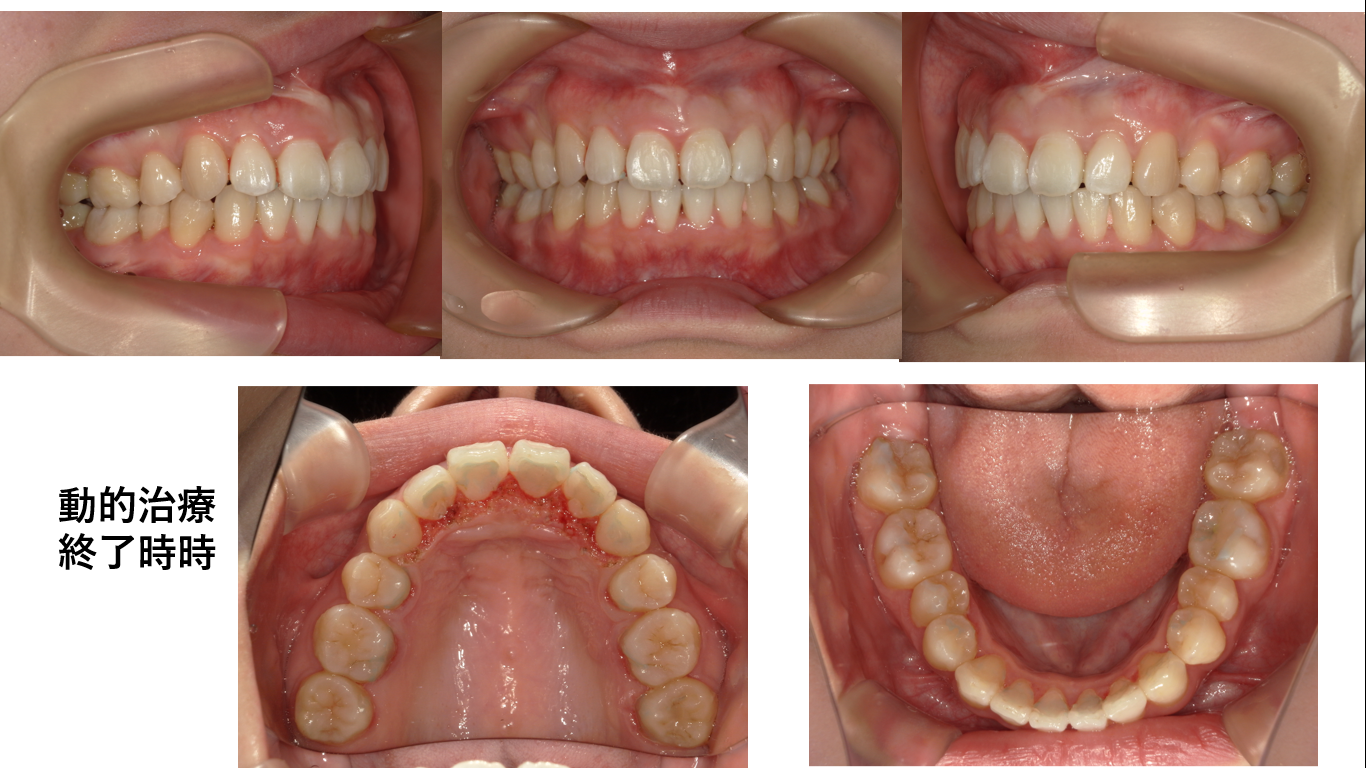

矯正症例147 AngleⅠ級 上顎前突 裏側矯正 舌側矯正

初診時23歳6か月、抜歯部位:上顎左右4番、上下顎左右8番、治療期間3年 治療費総額¥1,560,000(税込み)